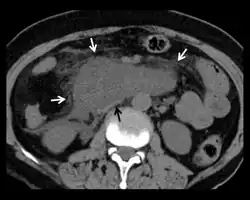

| Duodenum(marked) | |